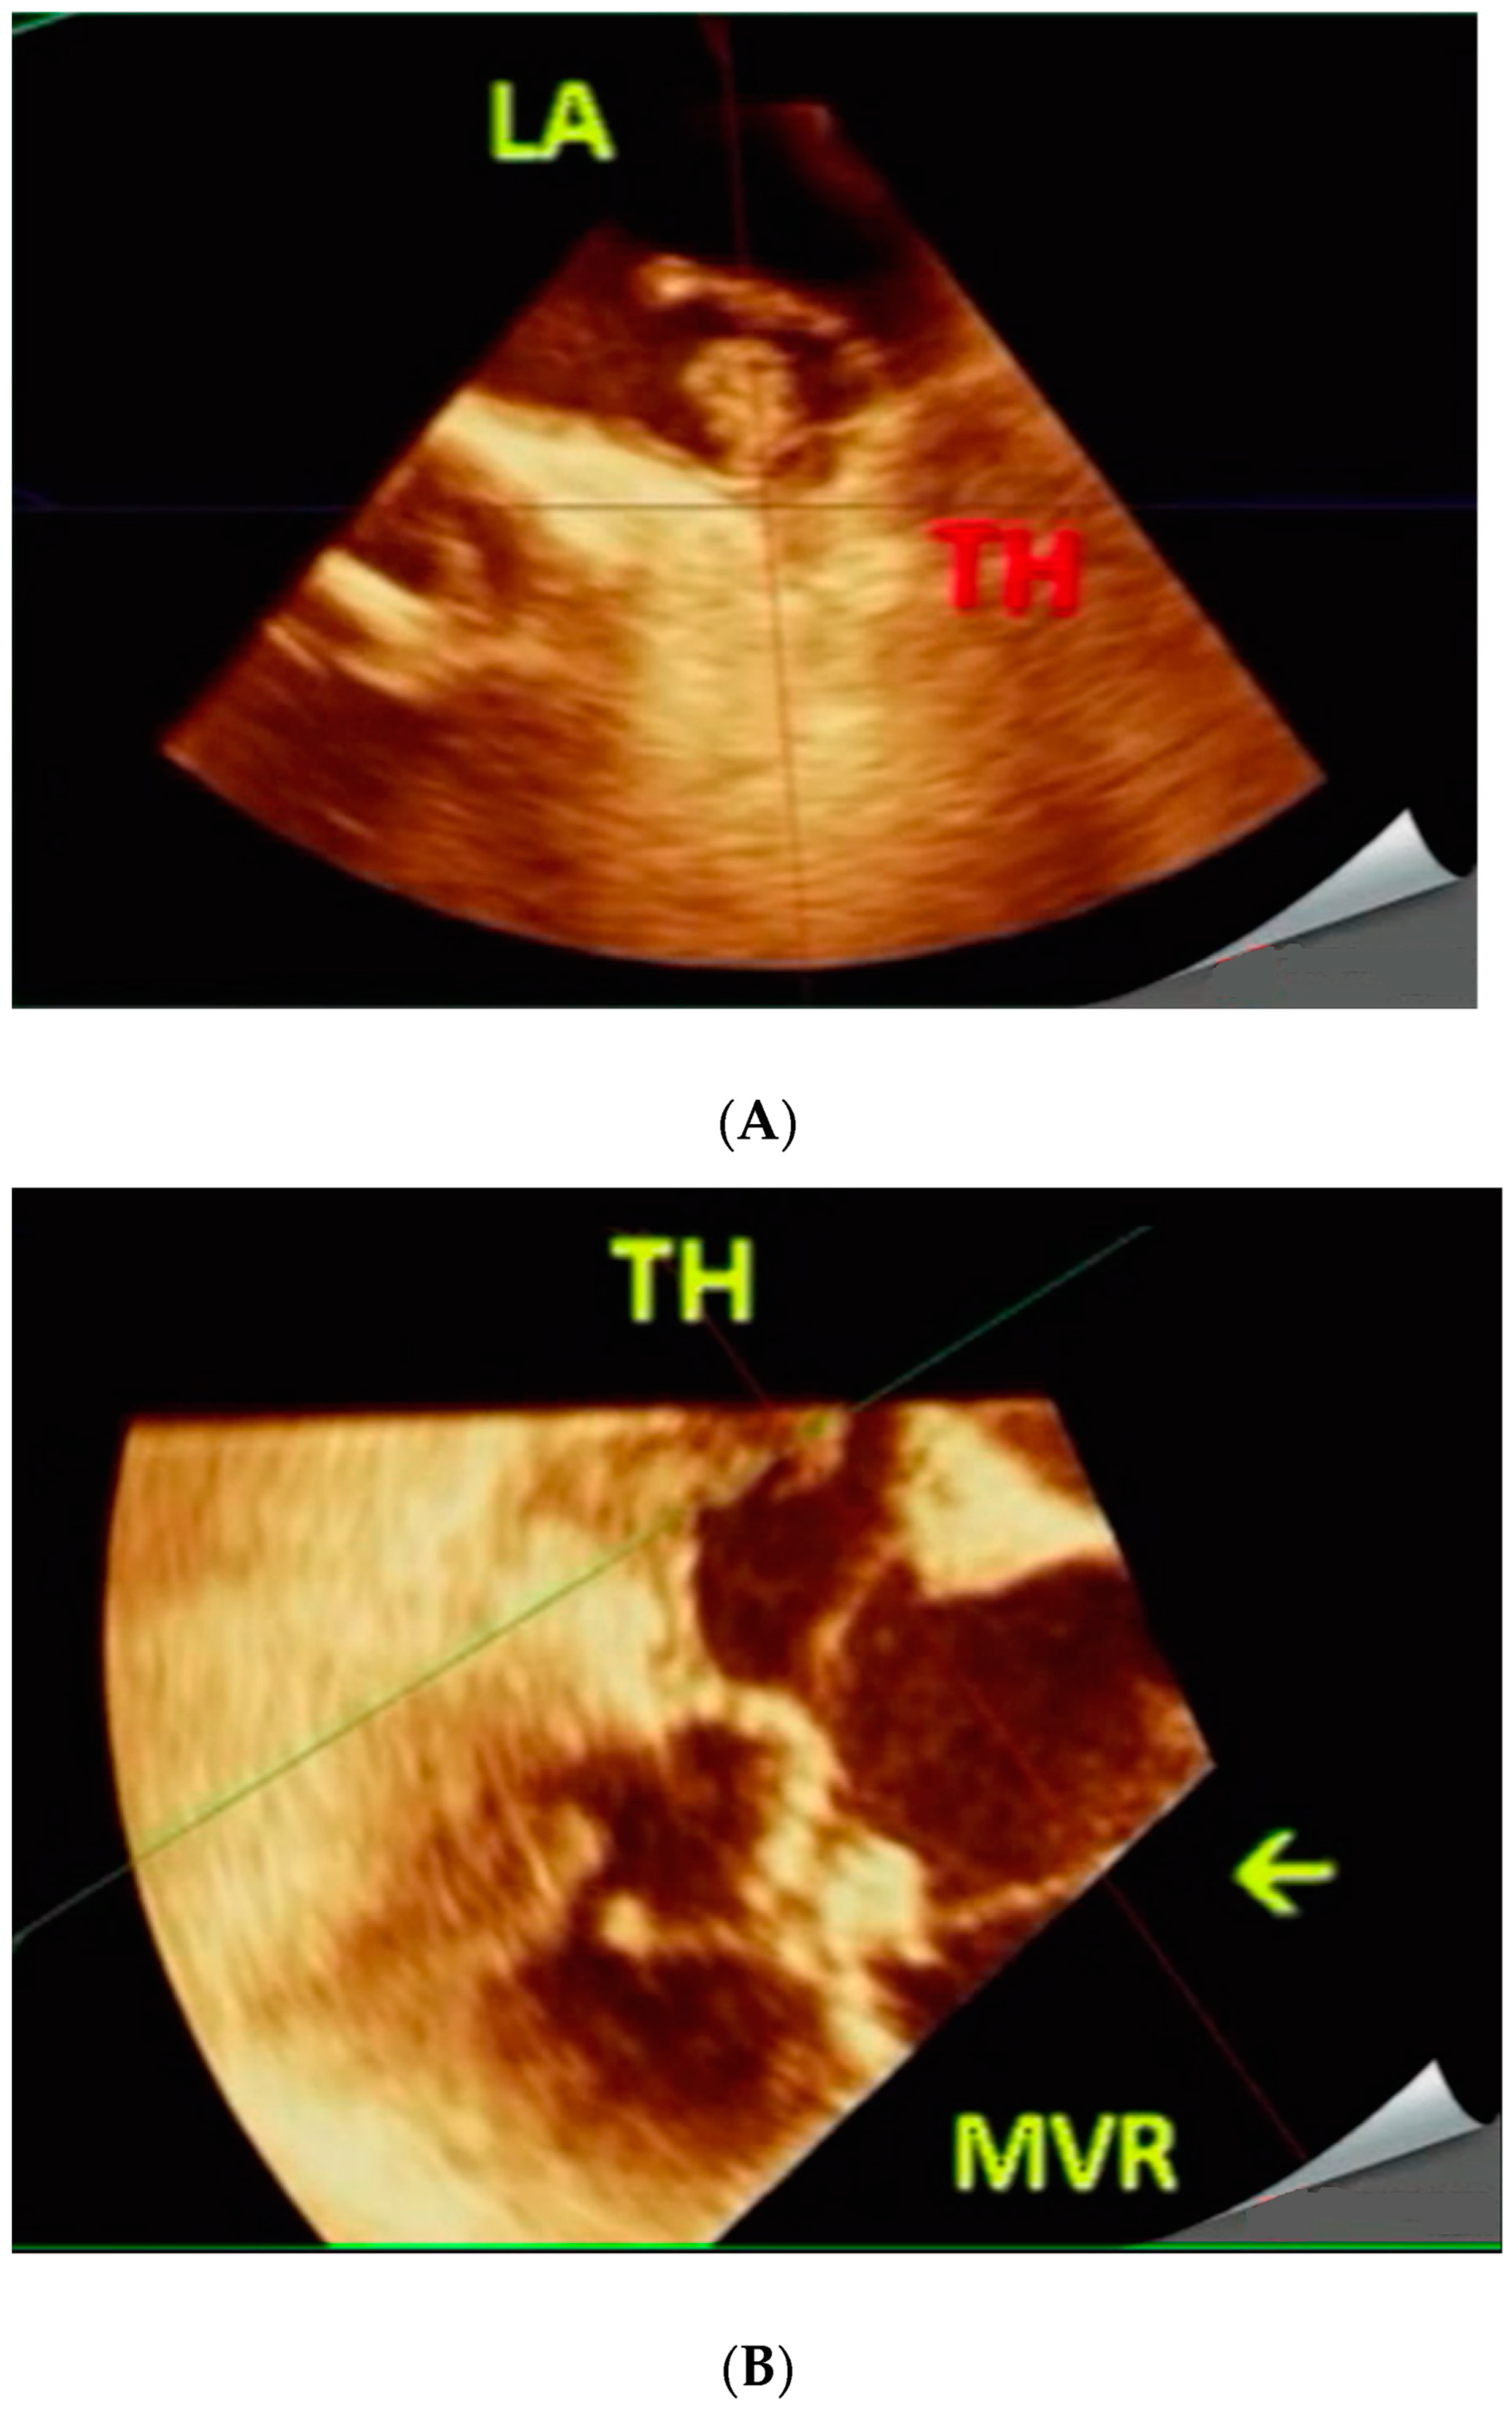

Figure 2. (A,B). 56-year-old female with severe MVR stenosis (Case 2). Pre-procedure. Live/real-time three-dimensional transesophageal echocardiography (A,B). A TH is noted in LAA and adjoining LA body in A. During procedure. The arrow in B points to the catheter deployment device passing through MVR avoiding the TH. Abbreviations as in Figure 1.

Figure 4. (A,B). 67-year-old male with severe MVR stenosis (Case 4). During procedure. Live/real-time three-dimensional transesophageal echocardiography (A,B). The arrow points to the catheter deployment device passing through MVR and bypassing the TH in MPR mode in A and in full volume mode in B Abbreviations as in previous Figures.